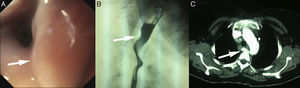

Presentamos el caso de una mujer de 45 años que consultó por un cuadro de disfagia intermitente tanto a líquidos como a sólidos, acompañado de vómitos ocasionales de 4 años de evolución. La paciente estaba en seguimiento por psiquiatría, por alteración de la conducta, y por endocrinología, por un bocio multinodular, sin presentar otros antecedentes de interés. En los últimos meses, la paciente refería que, la disfagia era más acusada, acompañada de una pérdida de 68kg de peso en los 3 últimos. Se le realizó una endoscopia digestiva alta (EDA), donde se objetivó un área pulsátil que ocluía levemente la luz del esófago en su tercio superior. Se completó el estudio con un tránsito baritado esófago-gástrico y una tomografía computarizada (TC). En el tránsito se observó una impronta esofágica sugestiva de compresión extrínseca en el tercio superior esofágico, confirmándose en la TC la existencia de una ASDA (fig. 1). Las modificaciones en la dieta y en la deglución fueron suficientes para mejorar el cuadro clínico, y la paciente se encuentra actualmente asintomática tras 4 años de seguimiento.

A) Endoscopia digestiva alta. La flecha señala un área pulsátil sugestiva de un vaso anómalo. B) Tránsito baritado. La flecha señala la impronta en el esófago, secundaria a una arteria subclavia derecha aberrante (ASDA). C) Tomografía computarizada. La flecha señala la ASDA, y cómo esta desplaza al esófago hacia la izquierda.

El diagnóstico puede pasar inadvertido con la EDA (hasta un 20% de los casos), que debe realizarse para descartar otras causas de disfagia1. Aquí sí se objetivó un área pulsátil sugestiva de un vaso anómalo, confirmándose posteriormente con el tránsito baritado y la TC. La angiografía permite identificar esta arteria aberrante y visualizar mejor el mapa vascular de la zona. Debido a que la angiografía es una exploración invasiva, creemos que debería ser utilizada, únicamente si se decide la corrección quirúrgica de la anomalía vascular. En este caso, la TC confirmó la presencia de la arteria aberrante, describiéndose una sensibilidad del 100% en algunos casos7. El tratamiento inicial de la disfagia lusoria depende fundamentalmente de la gravedad de los síntomas. En los casos leves-moderados, como en esta paciente, se debe empezar con modificaciones de la dieta, con un aumento de los alimentos de consistencia blanda y con raciones más pequeñas; así como con la reeducación de la deglución, comenzando por comer más despacio y masticar bien los alimentos3. Algunos estudios también muestran la mejoría de la disfagia añadiendo, además, inhibidores de la bomba de protones y/o procinéticos8. El tratamiento quirúrgico puede ser necesario si no mejoran los síntomas, a pesar de la dieta, o si existe una dilatación aneurismática cerca de la raíz de la arteria9,10. También influye la edad, puesto que en niños con clínica respiratoria o compresión esofágica la cirugía es el tratamiento de elección para evitar que empeoren los síntomas5. El tratamiento conservador, con la modificación en la dieta y en la deglución, mejoró la clínica de nuestra paciente, y ha permanecido prácticamente asintomática durante 4 años de seguimiento.